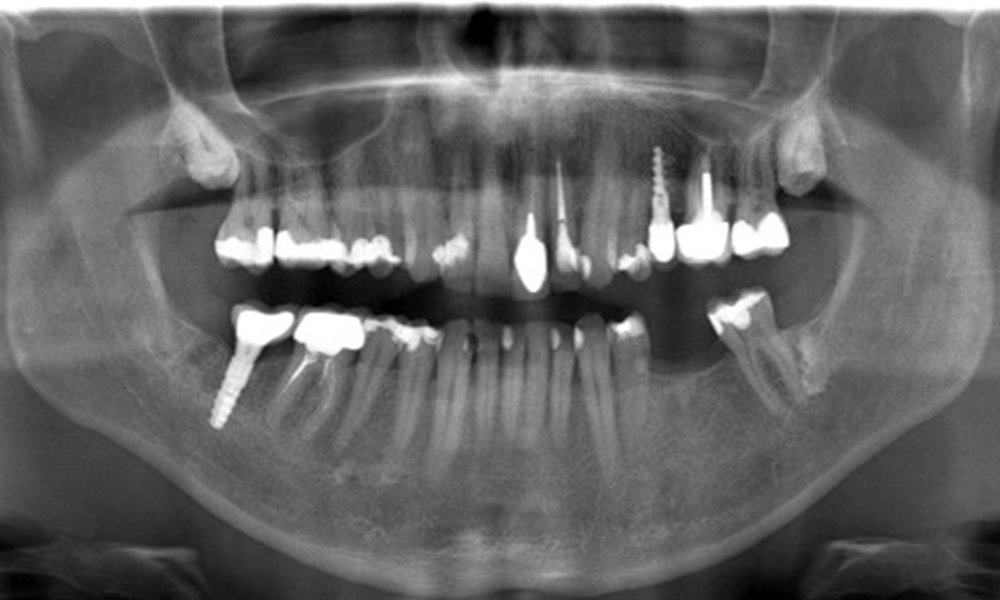

Der Patient hat einige zahnärztliche Restaurationen und zwei Implantate (2. und 4. Quadrant). Anhand der aktuellen Befunde lässt sich eine Gingivitis bei stabilem parodontalen Zustand am reduzierten Parodont (Stadium III, Grad A) feststellen.

Versorgungen: zahnärztliche Restaurationen (NEM keramisch verblendet), zwei Implantate (2., 4. Quadrant)